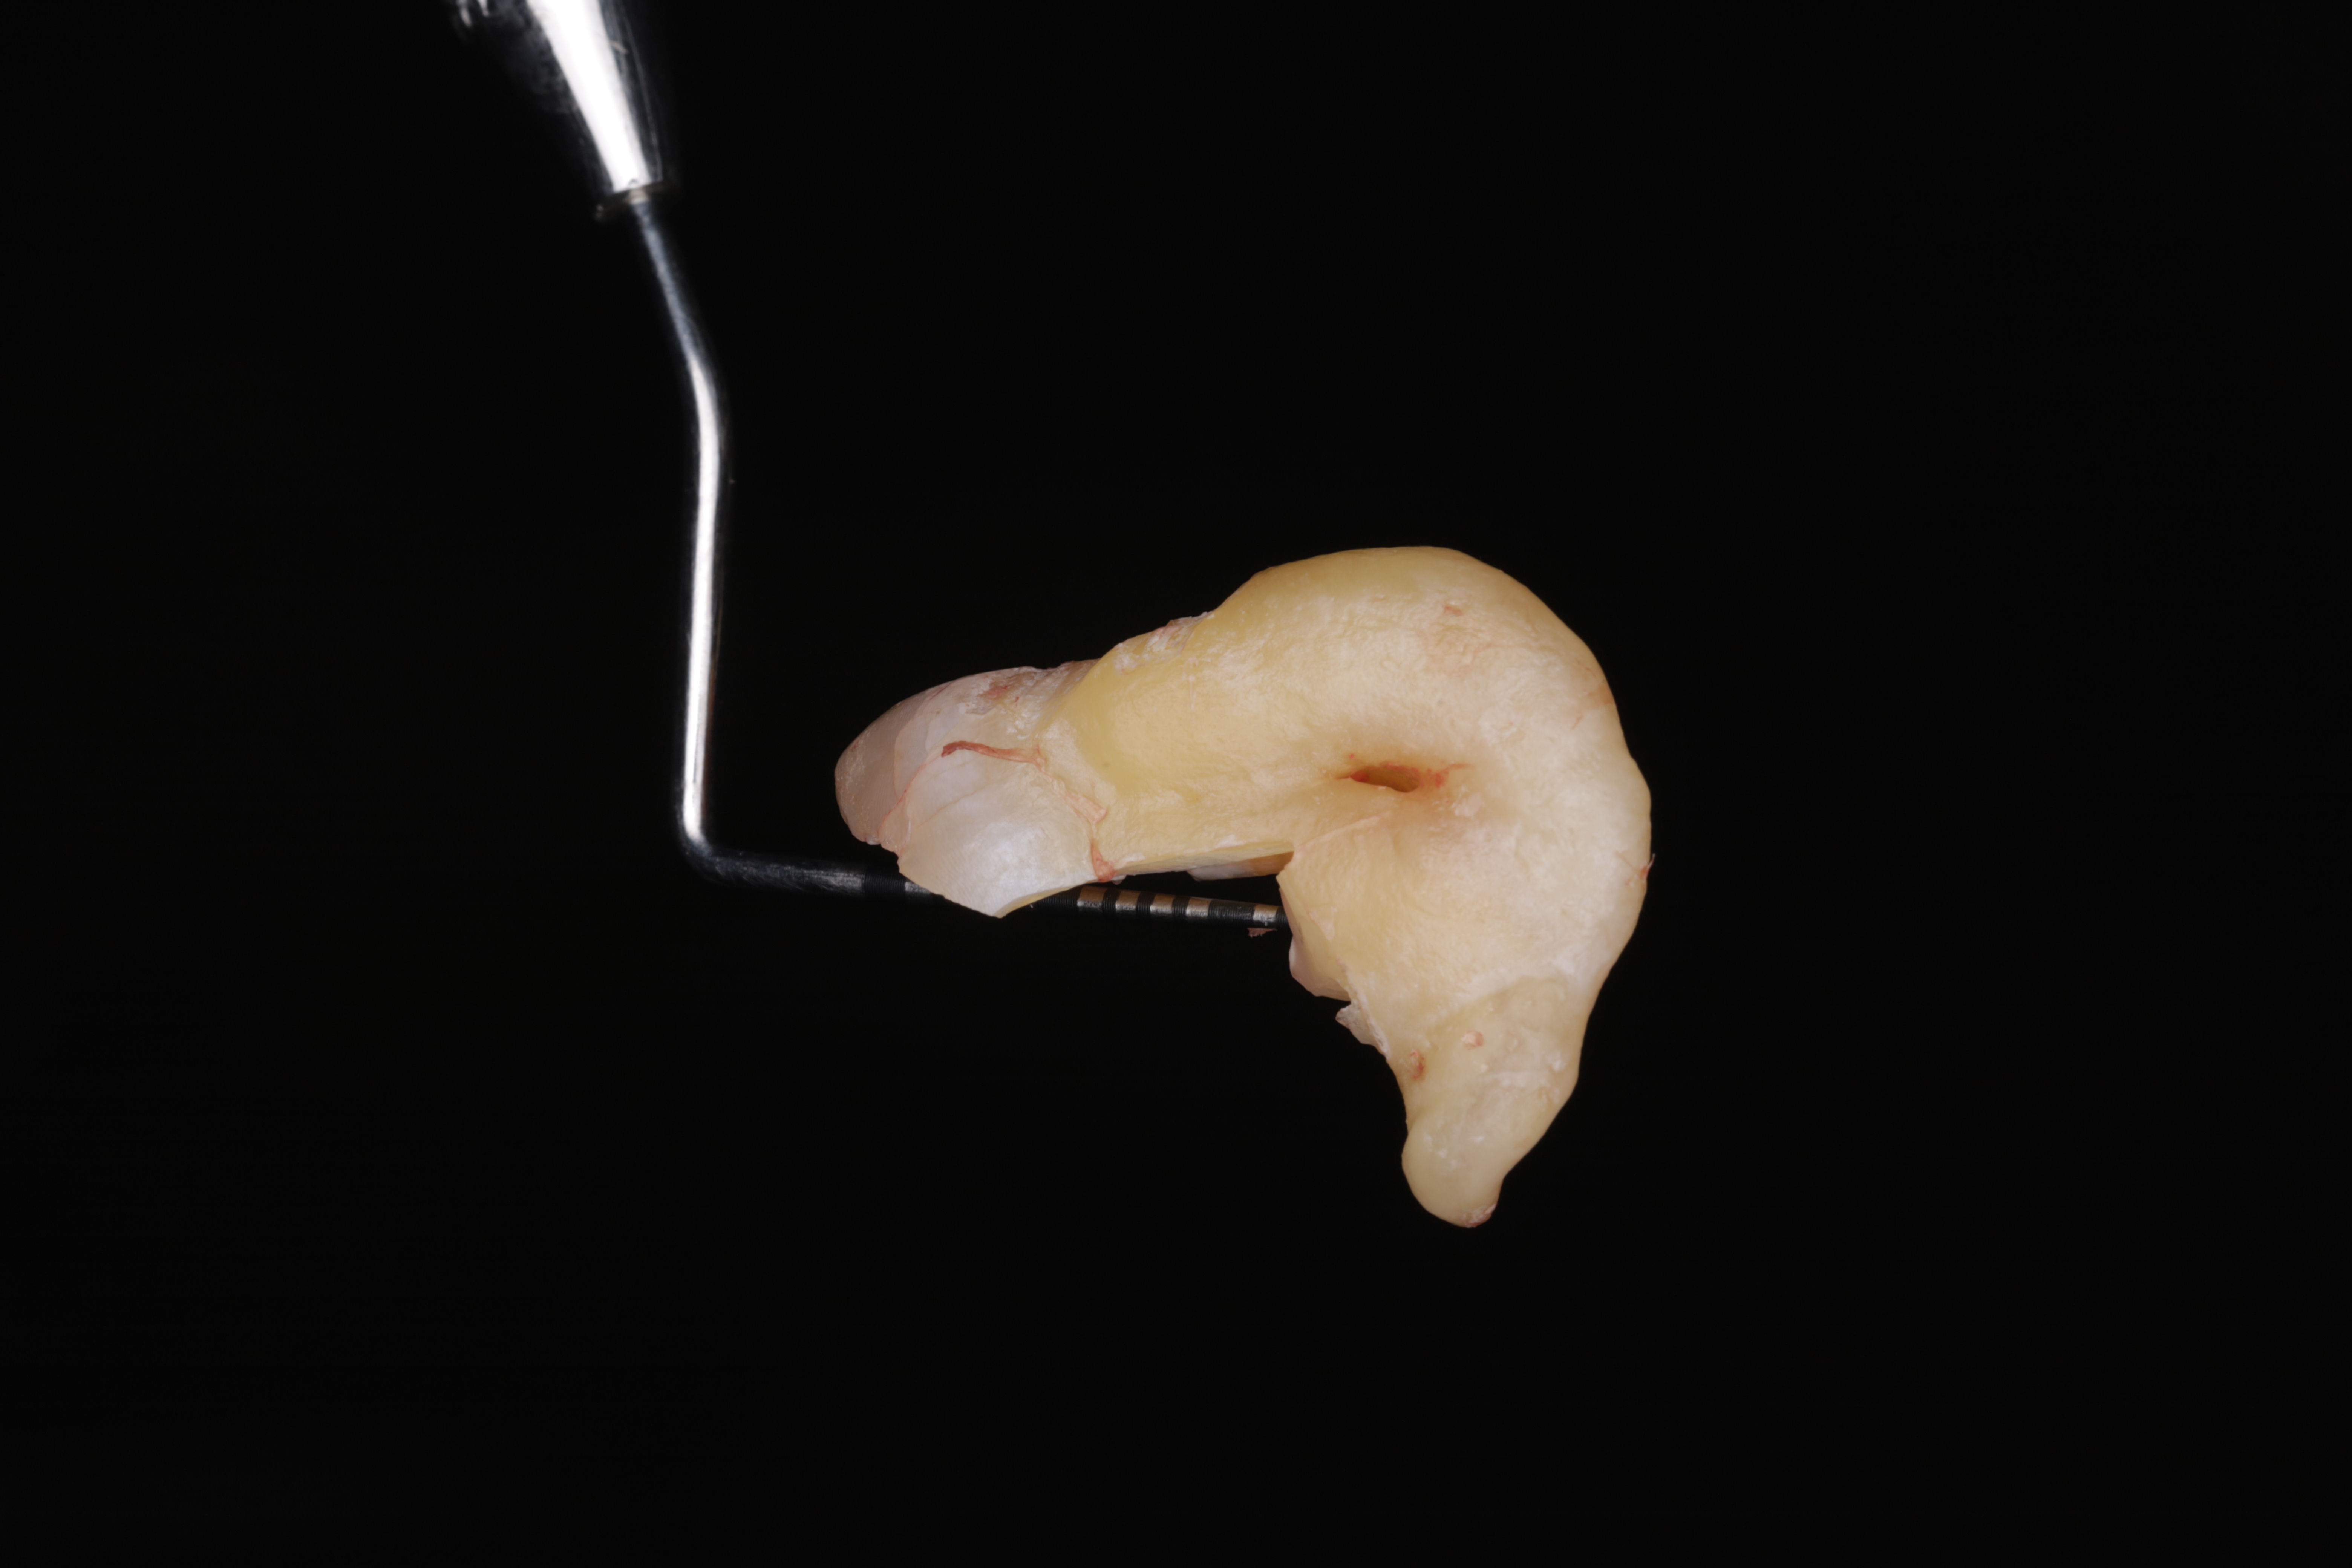

Зуб после удаления с приложенным пародонтальным зондом